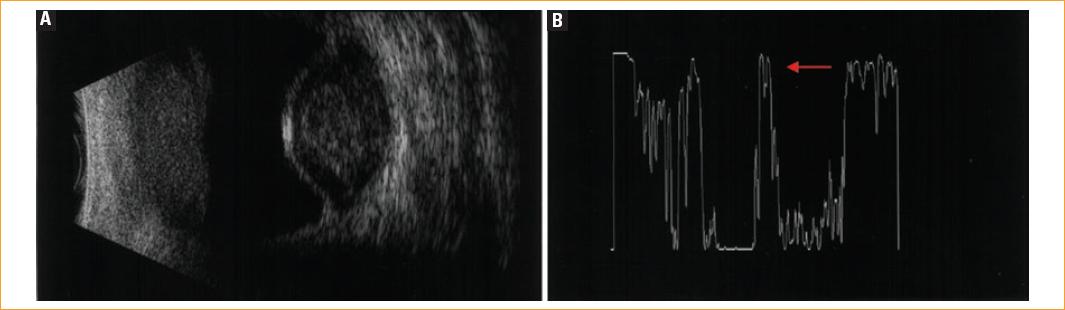

En B-scan, el DC se presenta como una membrana periférica fina, de superficie lisa y con forma de domo (Fig. 1 A), con espigas del 100% de amplitud en A-scan. En una inspección cuidadosa a baja ganancia, se puede observar un doble pico (Fig. 1 B). La evaluación cinética suele mostrar poco o ningún movimiento posterior (aftermovement)1.

Figura 1 Desprendimiento coroideo hemorrágico. A: ecograma B en corte transversal mostrando típica configuración en domo. B: ecograma modo A espiga de 100% de amplitud, en doble pico.